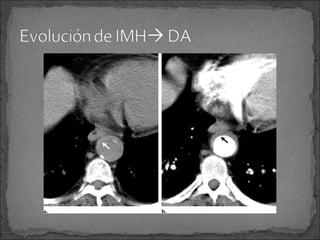

Algunos piensan que IMH aórtico es precursor de una

disección aórtica

Grosor del hematoma nos puede indicar la cantidad de

hemorragia que este tenga y su posibilidad de

evolucionar a disección aórtica.